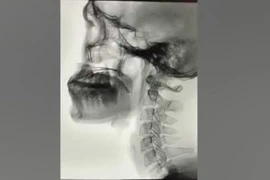

Bướu giáp khổng lồ là bệnh lý hiếm gặp, khối u kích thước lớn ảnh hưởng đến thẩm mỹ và chất lượng cuộc sống như gây khó nuốt, khó thở, run tay, khàn giọng… Phẫu thuật bướu giáp khổng lồ tiềm ẩn nhiều nguy cơ và tai biến.

Bệnh nhân S.B. 20 tuổi (Gia Lai) có khối bướu giáp từ nhỏ, nhưng không điều trị, gần đây bướu to chèn ép khiến anh khó thở, nuốt khó, không thể cúi,...